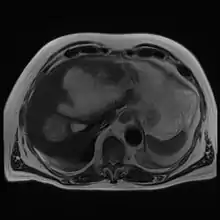

Amoebic liver abscess

A amoebic liver abscess is a type of liver abscess caused by amebiasis.[1] It is the involvement of liver tissue by trophozoites of the organism Entamoeba histolytica and of its abscess due to necrosis.